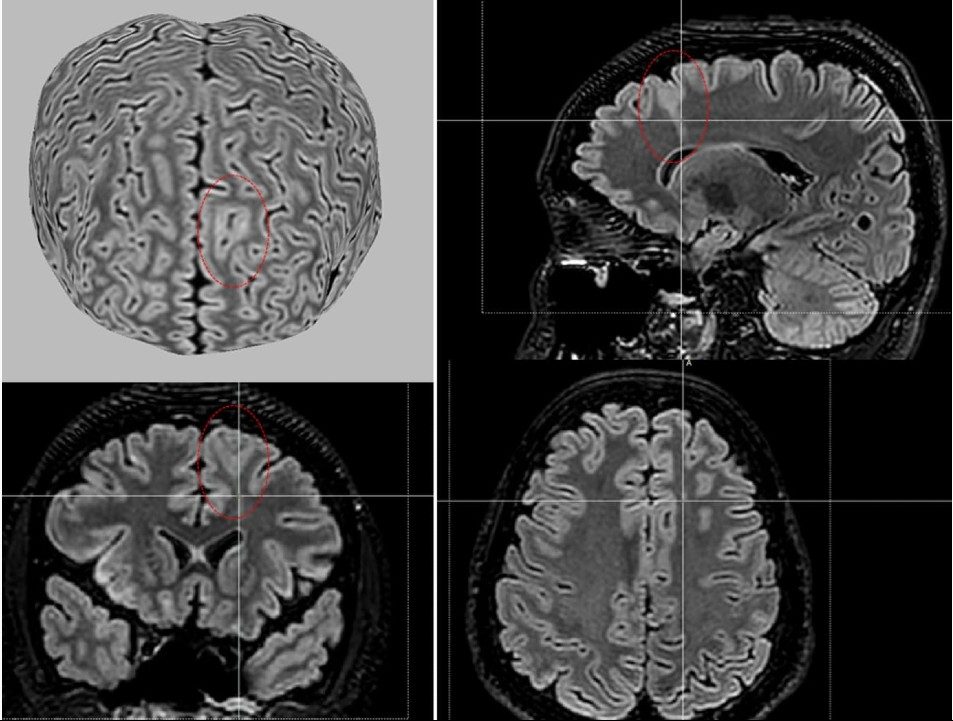

A partir de técnicas de aprendizado de máquina e da análise de dados de ressonância magnética de 1.185 participantes – incluindo 703 pessoas com displasia cortical focal e 482 controles – a ferramenta, denominada MELD Graph, conseguiu detectar as anormalidades a partir de varreduras nas imagens cerebrais.

A ferramenta, cujo algoritmo está disponível publicamente, detectou 64% das anormalidades cerebrais ligadas à epilepsia que os médicos radiologistas não haviam detectado. Com isso, a expectativa é que a MELD Graph possa atender a mais de 4 milhões de pessoas em todo o mundo que convivem com esta causa de epilepsia.

De acordo com Luca Palma, da Bambino Gesù Children’s Hospital, na Itália, o MELD Graph identificou uma lesão sutil que muitos radiologistas não perceberam em um menino de 12 anos que tinha crises epilépticas diárias e havia tentado nove medicamentos anticonvulsivos sem nenhuma melhora em sua condição. “Esta ferramenta pode identificar pacientes com epilepsia que podem ser tratados cirurgicamente e ajudar no planejamento cirúrgico – reduzindo riscos, economizando dinheiro e melhorando os resultados”, disse o pesquisador em comunicado à imprensa.